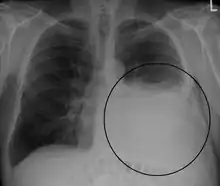

A pleural effusion appears as an area of whiteness on a standard posteroanterior chest X-ray.[12] Normally, the space between the visceral pleura and the parietal pleura cannot be seen. A pleural effusion infiltrates the space between these layers. Because the pleural effusion has a density similar to water, it can be seen on radiographs. Since the effusion has greater density than the rest of the lung, it gravitates towards the lower portions of the pleural cavity. The pleural effusion behaves according to basic fluid dynamics, conforming to the shape of pleural space, which is determined by the lung and chest wall. If the pleural space contains both air and fluid, then an air-fluid level that is horizontal will be present, instead of conforming to the lung space.[13] Chest radiographs in the lateral decubitus position (with the patient lying on the side of the pleural effusion) are more sensitive and can detect as little as 50 mL of fluid. Between 250 and 600mL of fluid must be present before upright chest X-rays can detect a pleural effusion (e.g., blunted costophrenic angles).[14]

Massive left-sided pleural effusion (whiteness) in a patient presenting with lung cancer.

Massive pleural effusion, later proven to be hemothorax in a South Indian male.